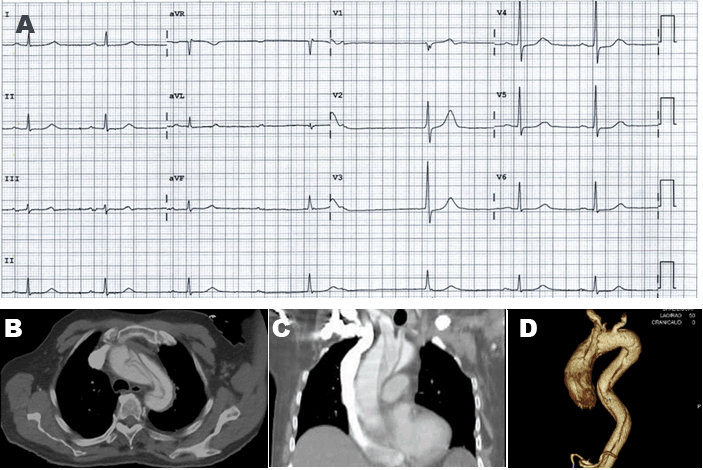

A 57-year-old male presented with bilateral arm paresthesia on a background of known hypertension and hypercholesterolemia, treated with irbesartan, hydrochlorothiazide and simvastatin. He had no family history of aortic syndromes or vasculitis. Blood pressure reading was elevated at 150/90, but was equal bilaterally, and an ECG demonstrated ST elevation in aVR with reciprocal ST depression in the anterior, inferior, and lateral leads (Figure 2A). High sensitivity troponin was mildly elevated at 20 ng/L (normal range <14 ng/L). He underwent urgent transradial coronary angiography which showed no flow limiting coronary artery stenosis, but was commenced on dual anti-platelets without heparinization. Following the procedure, his symptoms and ECG changes resolved, however he developed intense throat discomfort. The possibility of aortic dissection was raised and CT aortography confirmed type A aortic dissection from the aortic cusps extending into the brachiocephalic, left common carotid and subclavian arteries (Figure 2B). He subsequently underwent a successful aortic graft replacement.

Figure 2: (A) ECG demonstrating aVR ST elevation with reciprocal ST depression in leads I, II, III, aVF, V3-V6, (B, C) Contrast-enhanced CT demonstrating type A dissection extending from the aortic valve to the origin of the descending aorta, (D) A small amount of arterial contrast can be seen in the false lumen which may represent a fenestration.